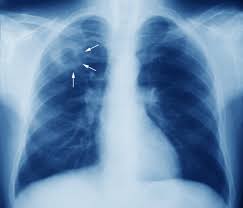

Monday: “Shared Pathogenomic Patterns Characterize a New Phylotype, Revealing Transition toward Host-Adaptation Long before Speciation of Mycobacterium tuberculosis” by Guillaume Sapriel and Roland Brosch, Genome Biology and Evolution

1. Tuberculosis

3. Mycobacterium